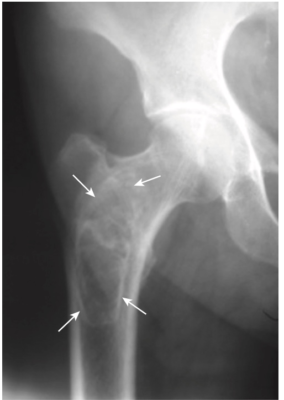

- Trên phim X quang thông thường, các ổ nhồi máu tủy xương cũ được nhìn thấy là các lắng đọng xương vô định hình, đậm đặc trong khoang tủy của các xương dài và thường được bao quanh bởi một lớp màng xơ cứng mỏng (Hình-8).

- Tăng rõ bè xương

- Bè xương thô và dày (Hình- 9).